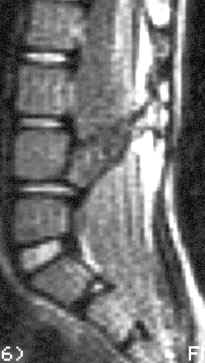

“Расщепленный спинной мозг” – выделяют два варианта этой патологии: диастематомиелия – когда костный “шип” (см.МРТ изображение) разделяет как спинной мозг, так и дуральный мешок на два отдельных “рукава”; дипломиелия – когда сам спинной мозг разделен на две половинки фиброзным тяжом и, все это находится в едином дуральном мешке. Симптоматика, показания к операции и результаты аналогичны описанным выше в разделе “Фиксированный спинной мозг” (“tethetred cord”). Операция состоит из “удаления шипа” и освобождения спинного мозга (“untethering”) путем иссечения конечной нити.